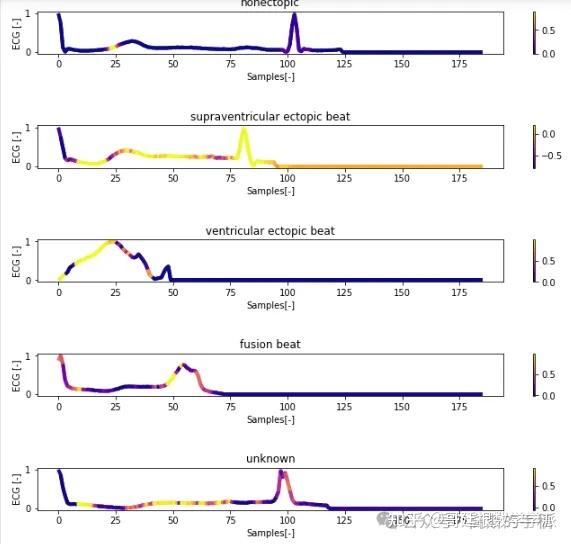

一维神经网络的特征可视化分析-以心电信号为例(Python,Jupyter Notebook)

包括Occlusion sensitivity方法,Saliency map方法,Grad-CAM方法